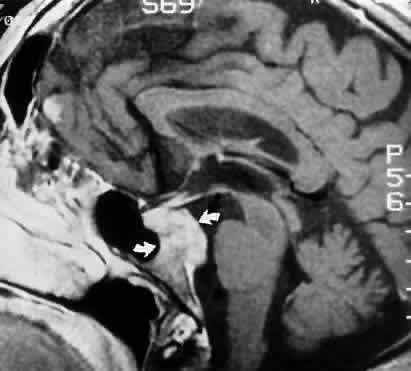

Acquired bi-nuclear total ophthalmoplegia is occasionally seen (Fig. 11), as reported by Masucci.82 These findings are the result of thrombotic or embolic processes at the level of the basilar bifurcation, with occlusion of the median mesencephalic perforating arteries. Congenital bilateral total ophthalmoplegia with or without levator and pupil sparing has been reported and may be associated with dysplasia of the corpus callosum.83

Fig. 11. Bilateral oculomotor palsies (nuclear?) associated with abrupt onset of vertigo and mild left hemiparesis.